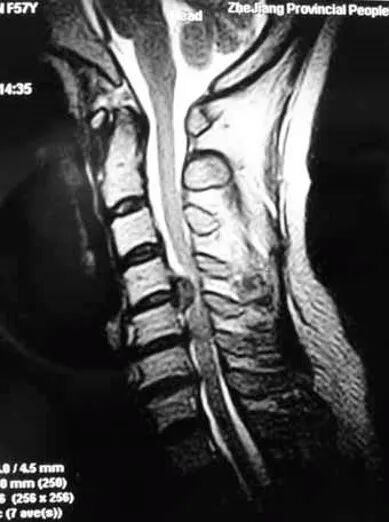

MRI成像显示颈椎椎间盘、椎体、韧带及脊髓,根据信号改变作出判断

脊髓型颈椎病MRI表现